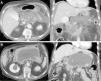

La pancreatitis aguda es una patología común y potencialmente grave que tiene un curso clínico muy variable. Este artículo pretende revisar el papel de las distintas técnicas de imagen en el manejo de esta entidad, describir sus principales manifestaciones radiológicas y la nomenclatura específica asociada a esta entidad.

Acute pancreatitis is common; the clinical course of this potentially severe condition varies widely. This paper aims to review the role of different imaging techniques in the management of acute pancreatitis, describe the main imaging findings for this entity, and explain the terms and criteria used to classify them.